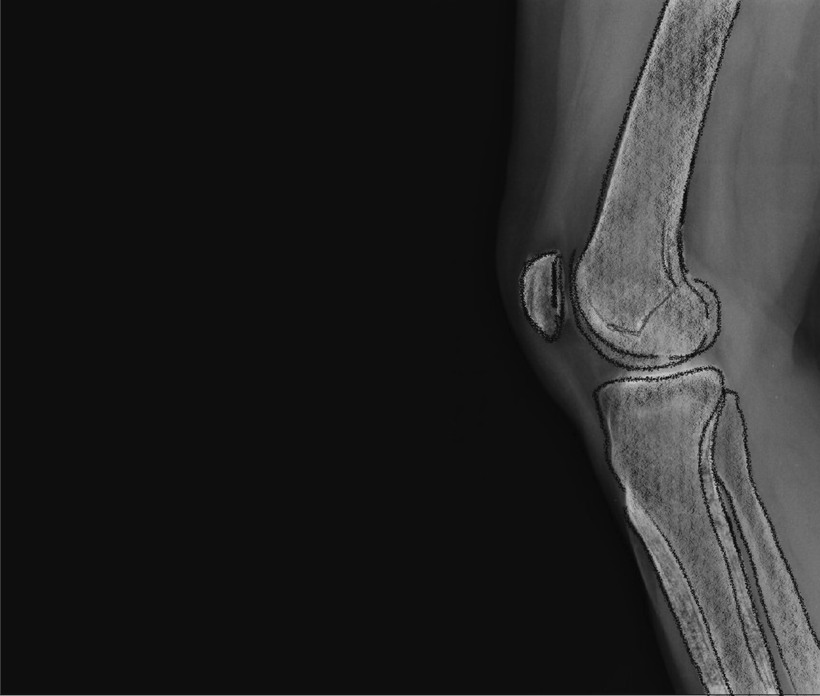

Orthopaedic Surgeon

Precision meets personality

Hamish McLaren needed a digital presence to match his expertise in robotic joint replacement. We designed a sleek, patient-friendly site paired with brand photography that captures his calm confidence and cutting-edge care.